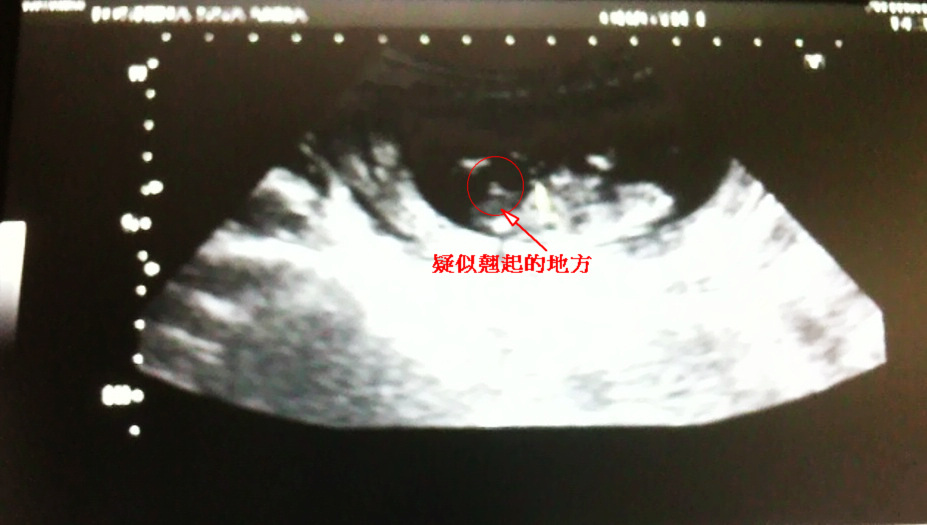

目前檢查的結果是在標準值內,屬於低危險群,我也放下心來。透過超音波我再次看到二寶在Grace裏頭動來動去,醫生在檢查的時候意外的發現有翹起的地方,還在這個地方標示了"m",有可能會是個男生,我開玩笑的醫生說有沒有看清楚丫,因為我跟Grace想要女生,醫生聽到我的反應,跟我說現在來太小,不太能夠確定,下個月來產檢的時候應該會比較清楚,回家的路上我跟Grace說,沒關係啦,第二胎如果是個男生,那就來生第三胎,拼拼看會不會是女的~哈哈

醫生說疑似的位置

超音波的影片,醫生還一直畫圈圈跟我們解釋翹起的地方